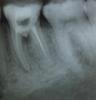

ANNA10 Опубликовано 4 июня, 2010 Автор Поделиться Опубликовано 4 июня, 2010 Врач сказал что каналов 4.но не сказалс колько запломбировалНачиталась форумов и везде советуют сходить к другому врачу Что я вчера и сделала. Она сделала снимоки сказала,что не запломбирован канал. И про бифуркацию тоже сказала.пообещала попробовать запломбировать каналы заново и закрыть бифуркацию очень дорогим лекарством.Может стоит попробовать?НЕ представляю как я смогу расстаться с мои зубиком! Сейчас вроде не сильно болит. Ссылка на комментарий

Бело4ка Опубликовано 4 июня, 2010 Поделиться Опубликовано 4 июня, 2010 Перфорация очень большая. По снимку так вообще как-будто корни разделились. И воспаление там есть, а как следствие деструкция кости. Прорут только закроет дырку, но не факт что кость там восстановится. Да и ортопед вряд ли захочет протезировать такой зуб. Ссылка на комментарий

Бело4ка Опубликовано 4 июня, 2010 Поделиться Опубликовано 4 июня, 2010 (изменено) Еще вчера смотрел хирург. Он сказал вырвать никогда не поздно И он может попробовать почистить зуб со стороны десны или распилить зуб на две части, почистить, а потом поставить вкладку и коронкувкладки и коронкивместо одного зуба получатся 2 маленькихда и на каждом из корней воспаление в районе верхушек тоже есть Изменено 4 июня, 2010 пользователем Бело4ка Ссылка на комментарий

ANNA10 Опубликовано 9 июня, 2010 Автор Поделиться Опубликовано 9 июня, 2010 Здравствуйте! Сегодня была у стоматолога. Я у нее спросила, что может вырвем и не будем мучаться? Она предложила попробовать, получется где-то 50 на 50. Запломбировала третий канал и положила временную пломбу. В пятницу сказала придти, закроет бифуркацию прорутом и поставит пломбу. И сказала , что скорей всего все будет нормально. Вот снимок Скажите, а то что вышел пломбирововочный материал за верхушку - это очень плохо? Ссылка на комментарий

Бело4ка Опубликовано 9 июня, 2010 Поделиться Опубликовано 9 июня, 2010 Скажите, а то что вышел пломбирововочный материал за верхушку - это очень плохо?Да тут уже не важно. Корни отдельно, от коронки ничего не осталось. Подумаешь, материал какой-то за верхушкой. Ссылка на комментарий